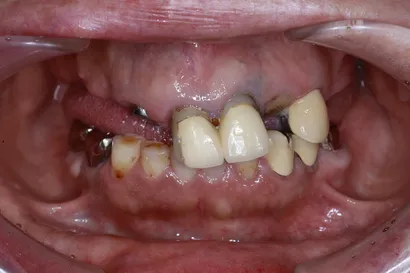

入れ歯からの全顎インプラント治療

60代 男性

執刀医 Dr.大杉 治療内容 他院で製作した入れ歯が「食べにくい・話しにくい・外れる」とお悩みで来院された患者様です。上顎は4本のインプラントで入れ歯を支える「オーバーデンチャー」としました。上あごを覆う部分をなくせるため、発音や食事がしやすくなります。下顎は「オールオン4」で歯をしっかり固定し、機能的に大変ご満足いただけました。

上顎:インプラントオーバーデンチャー(インプラントを支えにした義歯)

下顎:ピンクポーセレンを用いたチタンフレーム入りのフルジルコニアインプラントブリッジ治療期間 1年 費用 上顎:210万 税抜

下顎:330万 税抜リスク インプラントオーバーデンチャーを固定している連結部分の部品(ゴムなど)は、毎日のご使用で少しずつすり減る消耗品です。緩みの原因になるため、定期的なメンテナンスで状態をチェックし、必要に応じて交換していきましょう。 -